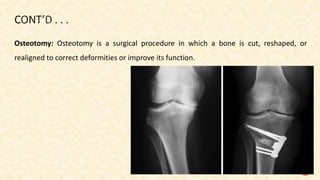

Osteotomy: Osteotomy is a surgical procedure in which a bone is cut, reshaped, or

realigned to correct deformities or improve its function.